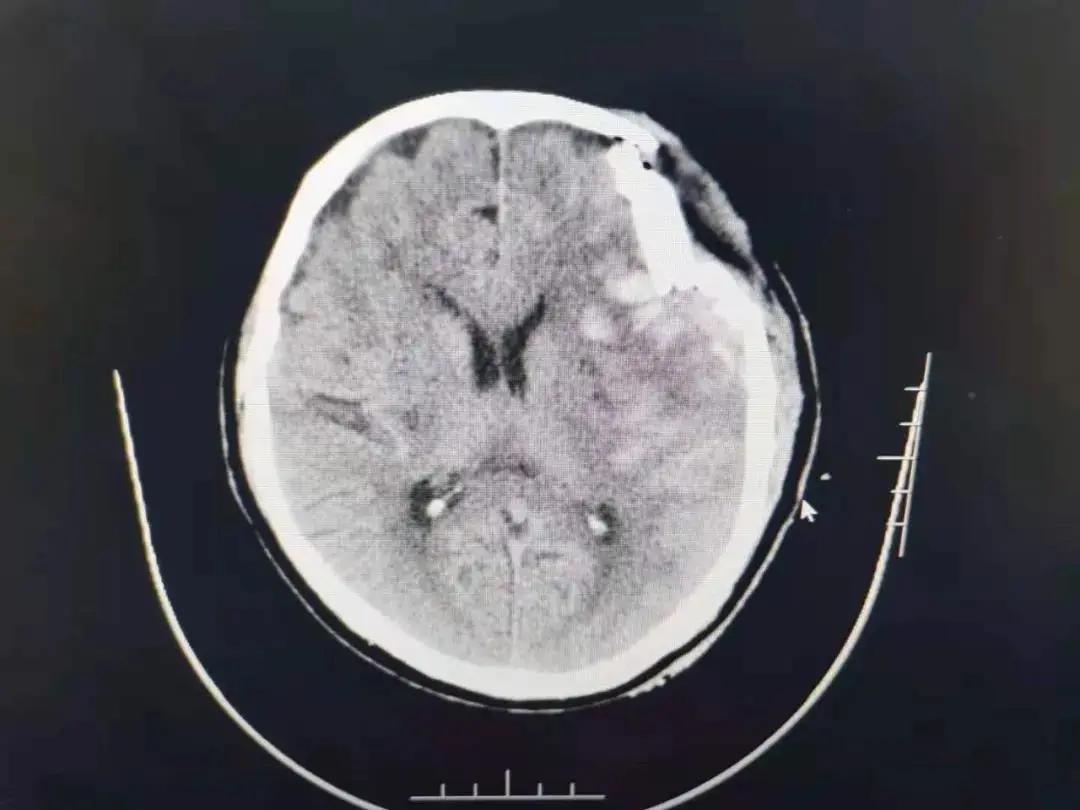

家住萧县白土镇的潘大爷在回家途中,因意外摔伤头部,急到萧县人民医院就诊,头颅CT显示:粉碎性凹陷性颅骨骨折、脑挫伤、脑内血肿。潘大爷处于昏迷状态,左颞顶部挫伤、肿胀,其上有一长约7㎝的伤口,有脑组织外溢,颅骨凹陷明显,病情危急,需急诊开颅手术,事不宜迟,必须争分夺秒。生命重于泰山,面对病人危重的病情,急诊科、神经外科医生响应迅速,立即组织专家进行综合会诊,认为患者情况危急,必须马上手术,在和家属充分沟通基础上,家属同意实施手术抢救。

经过相关检查和评估,在神经外科、麻醉科、手术室等多学科的紧密协作下,神经外科副主任武宏和马涛、纵锋两位医师立即实施手术抢救。虽然夜色已深,神经外科的医生们仍在沉着冷静地进行着一场与时间赛跑的生命拉力赛。经过近3个小时的努力,手术于早上5:05分顺利完成,术后患者转入ICU监护治疗。此次手术风险高,难度大,病人伤情严重,病情危急。医生们面对危急的病情,顺利完成“颅骨碎骨片清除+血肿清除+挫损失活脑组织清除术”,实现了萧县人民医院在颅脑损伤领域新的突破,标志着人民医院神经外科手术水平再次迈向上新的台阶。